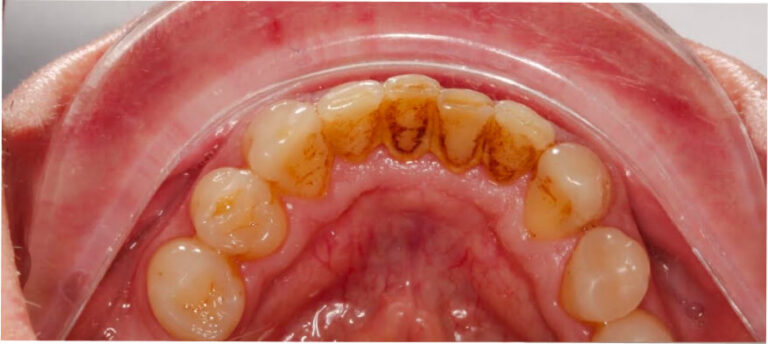

Po

Higienizacja